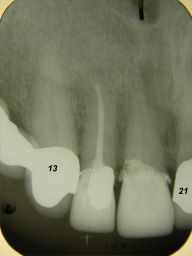

Das etwas dunkle Röntgenbild links(6/2003) zeigt diverse Probleme. Hier interessiert, daß der Zahn 22 (sprich: "zwei", "zwei") am 28.10.05 Schmerzen bereitete, weil der Zahnnerv unter Eiterbildung abgestorben war. Es brauchte 3 medikamentöse Einlagen, bis der Zahn ruhig war und am 18.11.05 eine Wurzelfüllung und einen Titanstift in den Wurzelkanal bekommen konnte. Bei der anschließenden Röntgenkontrolle rechts fiel der schlechte Randschluß der Krone 22 auf.

Weil auch die anderen Schneidezahnkronen (12-22) durch Randreparaturen und den schlechten Randschluß erneuerungsbedürftig aussahen, wurden 4 Einzelkronen geplant. Vorher hieß es aber noch, die schlechte Wurzelfüllung im Zahn 12 (Röntgenbild links) besser zu machen. Hierfür wurden am 17.2.06 die alten Kronen 11 und 12 entfernt. Rechts das Bild nach Entfernung von alten Füllungen und Karies.